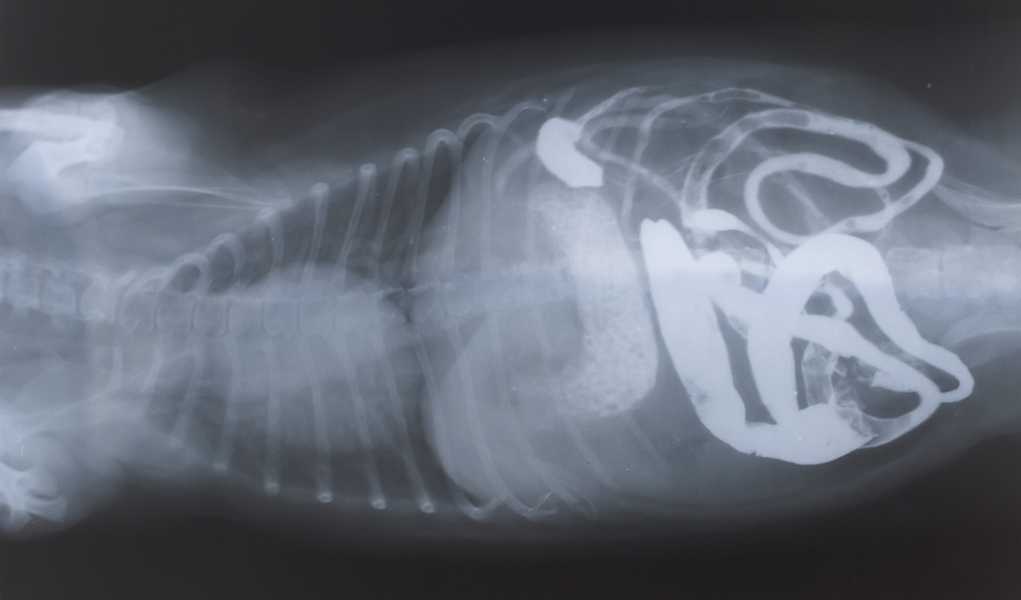

Истончение костей у кошек: причины и решения

Раздел: Мудрость в объективе